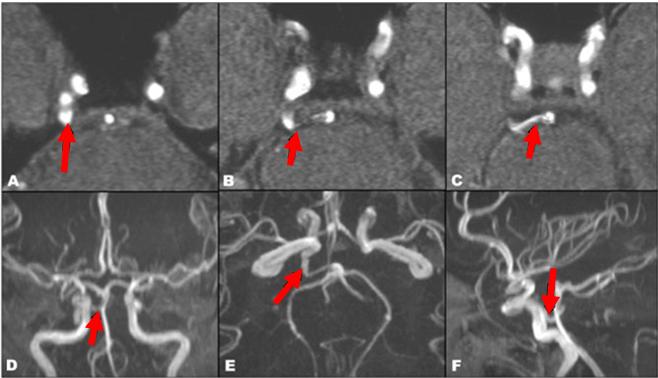

Hình 2. Hình ảnh động mạch tiểu não sau dưới (vị trí mũi tên chỉ) dài bất thường,

uốn cong quanh cầu não bên phải, đè ép rễ dây số V cùng bên.

Bệnh nhân Nguyễn Thị CH., 67 tuổi bị đau dây V nhánh hàm dưới (V3) bên phải hơn 2 năm. Bệnh nhân đã được điều trị nội khoa phối hợp nhiều loại thuốc nhưng không hết cơn đau, hay tái phát và mức độ đau càng ngày càng tăng, số cơn dày hơn. Bệnh nhân được xạ phẫu Gamma Knife tại Trung tâm Y học hạt nhân và Ung bướu Bệnh viện Bạch Mai với liều 35Gy (50% liều). Sau 4 tuần, bệnh nhân không còn biểu hiện đau và hiện không phải dùng thuốc.